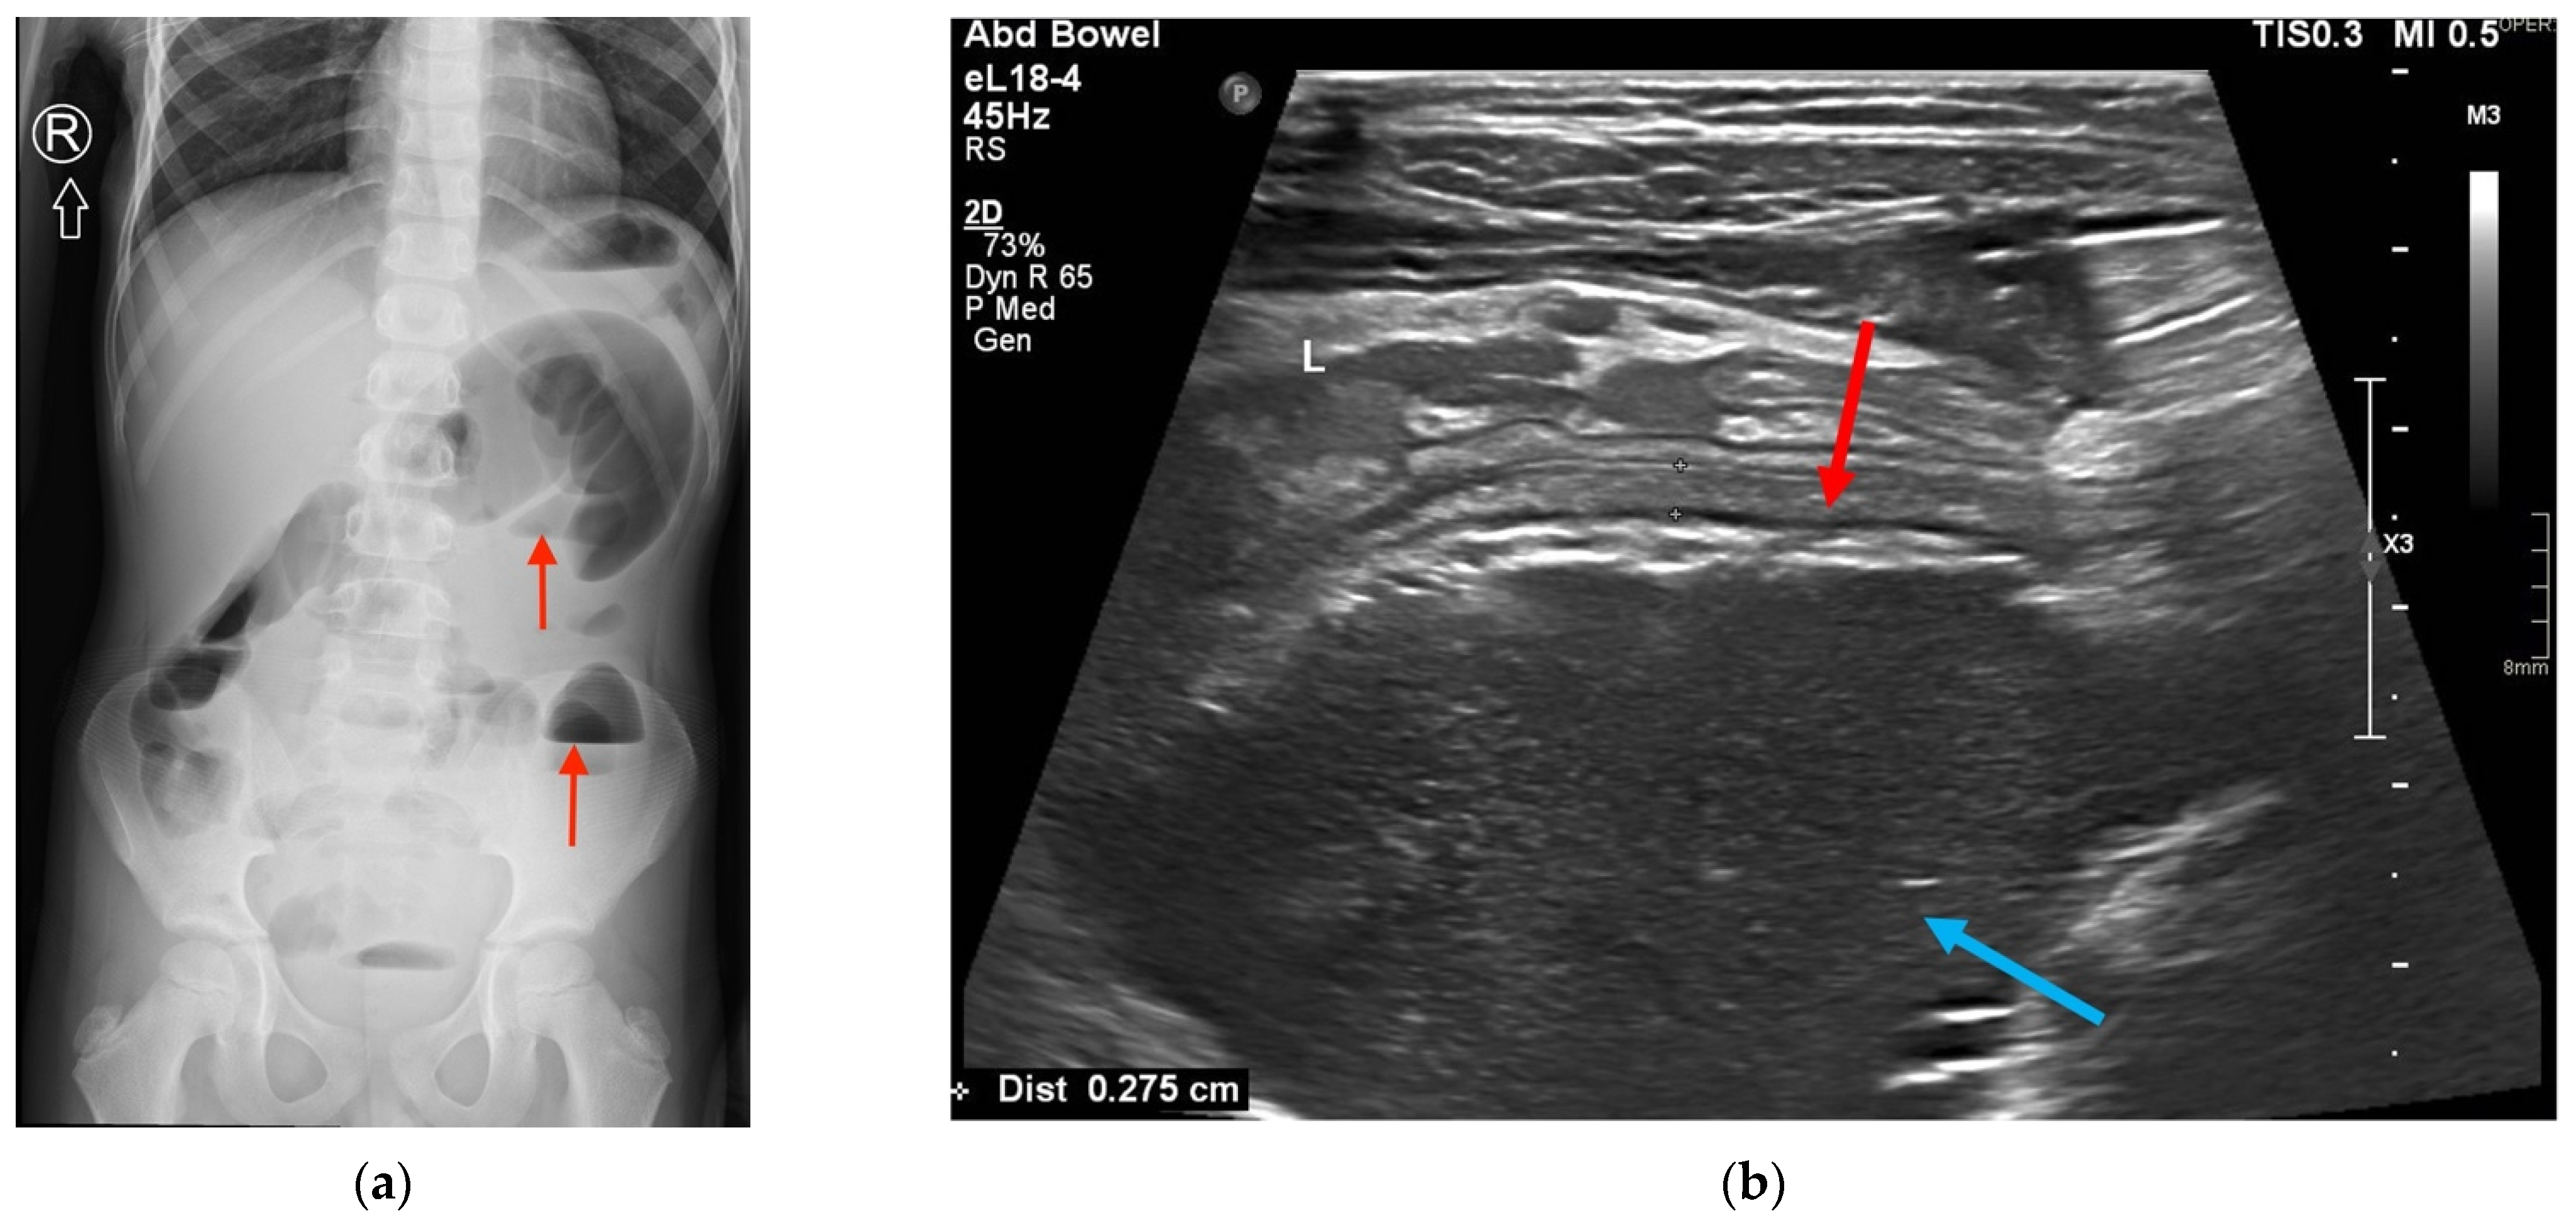

2. Case Presentation